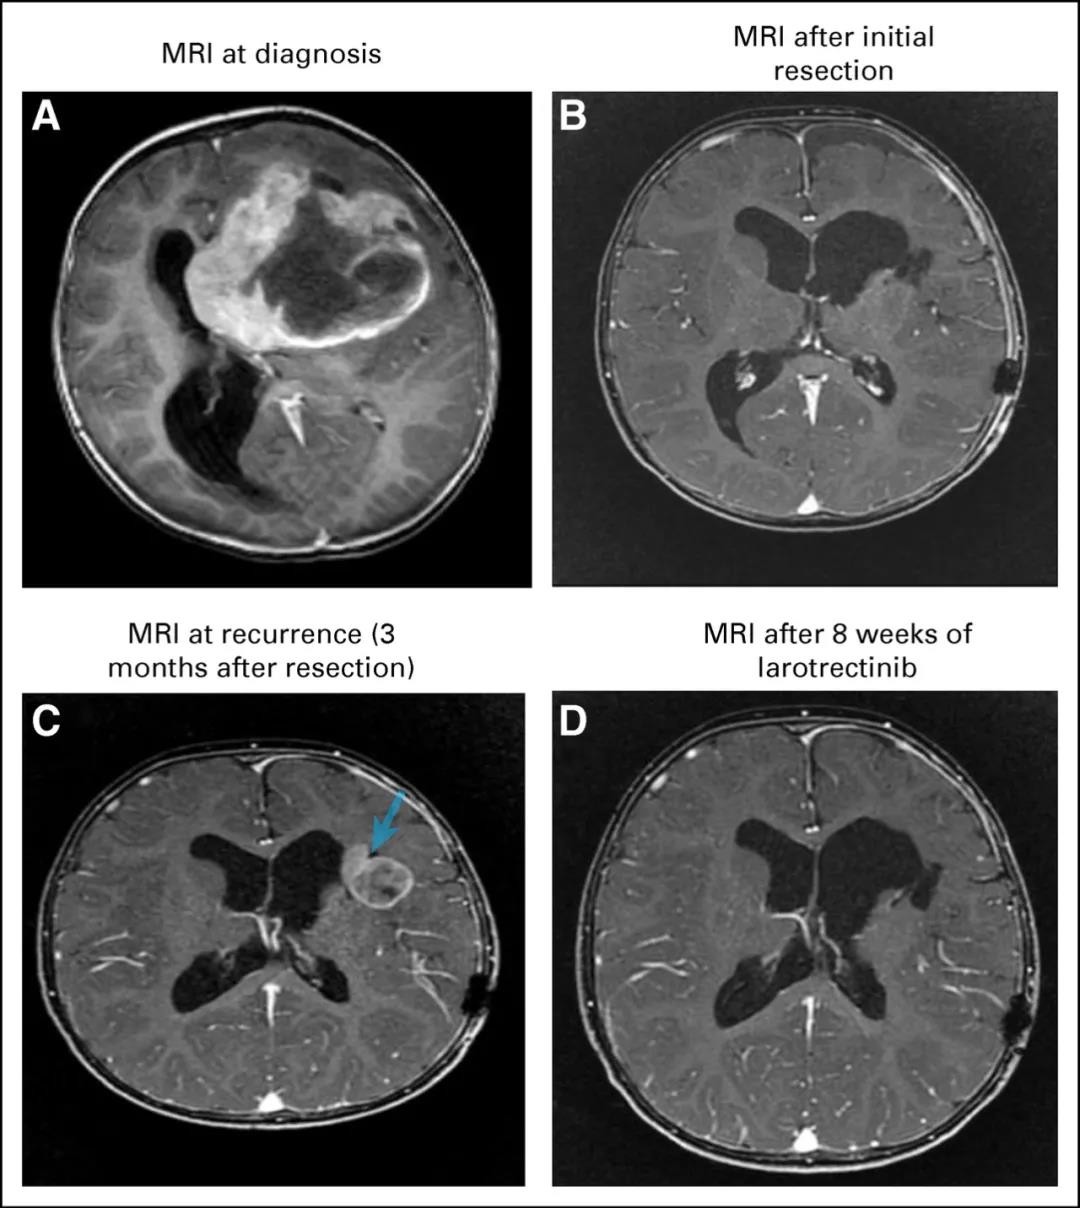

胶质母细胞瘤ETV6-NTRK3融合肿瘤快速消退